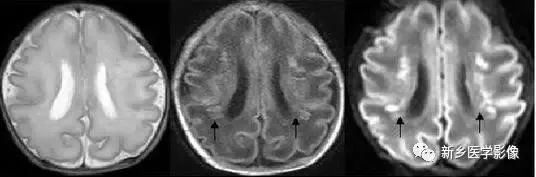

❺ 脑室周围白质软化症

主要与缺血缺氧及感染有关。常见于早产儿,是造成早产儿脑瘫的主要原因。

由于脑室周围白质的血供分别来自脑室区和远脑室区的终动脉,未成熟儿终动脉深穿支的侧支循环尚未建立,而胚胎晚期脑室周围白质对缺血缺氧敏感,所以,脑室周围自质软化症多见于早产儿。

由于病灶常为双侧性,故双侧侧脑室多同时扩大。脑白质内软化灶在CT扫描时表现为白质内斑片状低密度灶,MR上T1加权图呈低信号,T2加权图呈高信号。